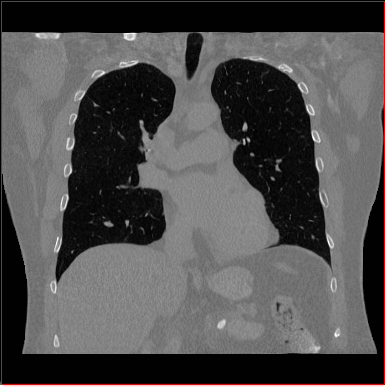

Chest Region

1×1×11\times 1\times 1

mm

384×384×384384\times 384\times 384

Figure 4: MAISI-v2 segmentation-guided results for small to large volume size and three different regions.